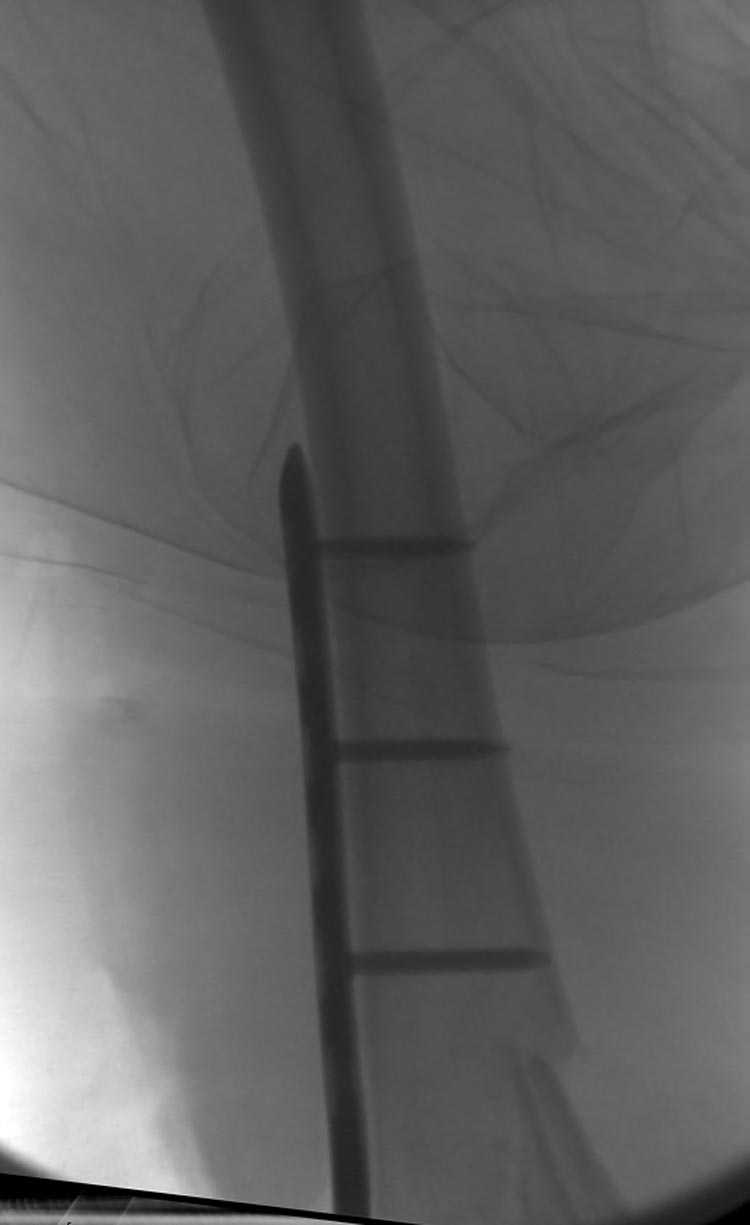

Это перелом не нижней трети, а дистального суставного конца, с распространением на диафиз. Что-то между C2 и C3. Но пока ближе к C2 по увиденному - вторую проекцию еще не показали.

Полноценная артротомия - зачем? Нужна была бы только ограниченная артротомия, если есть смещение фрагментов суставной поверхности, которое закрыто (всякого рода джойстиками) не устранить. Такого смещения тут не видно. Поэтому можно наложить спицевой дистрактор и заштифтовать закрыто.

На профиле стало видно, что открываться придется, это перелом C3, хотя можно назвать и C2+, т.е. с еще и фронтальным раскалыванием одного мыщелка. Надо сделать медиальную артротомию, ступеньку на внутреннем мыщелке устранить, ввести либо несколько временных спиц спереди назад, или сразу винт вдоль эллипса мыщелка. А дальше как выше написано - дистрактор, и штифтовать. Учитывая наличие открытого колена - вполне уместно ретроградно.